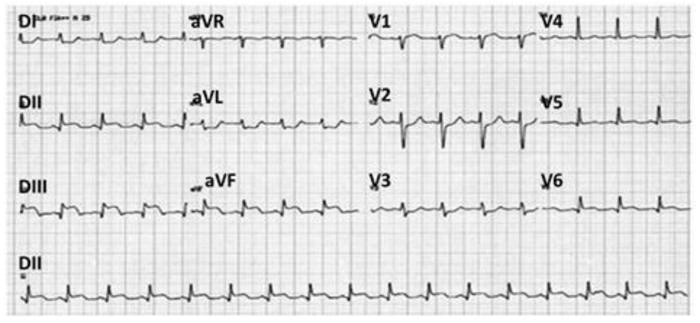

Homem de 70 anos, hipertenso e ex-tabagista com elevada carga tabágica, é admitido na emergência após episódio de síncope.

O evento ocorreu subitamente após forte estresse emocional e foi precedido por dor torácica de forte intensidade com irradiação para o

pescoço e mandíbula descrita como “em facada”. Nega náuseas, vômitos ou episódios prévios. Em uso de enalapril e sinvastatina.

Ao exame: taquipneico em ar ambiente, ansioso, com fácies de dor, sudoreico. FC 115 bpm, PA: 120x70 mmHg no membro superior direito e

90x50 mmHg no esquerdo. Ritmo cardíaco regular em 2 tempos, com sopro diastólico aspirativo nos focos aórtico e aórtico acessório 2+/6+.

Pulso radial esquerdo impalpável. Restante do exame físico sem alterações. O eletrocardiograma de admissão está a seguir.

A imagem é compatível com o diagnóstico de

Homem de 70 anos, hipertenso e ex-tabagista com elevada carga tabágica, é admitido na emergência após episódio de síncope.

O evento ocorreu subitamente após forte estresse emocional e foi precedido por dor torácica de forte intensidade com irradiação para o

pescoço e mandíbula descrita como “em facada”. Nega náuseas, vômitos ou episódios prévios. Em uso de enalapril e sinvastatina.

Ao exame: taquipneico em ar ambiente, ansioso, com fácies de dor, sudoreico. FC 115 bpm, PA: 120x70 mmHg no membro superior direito e

90x50 mmHg no esquerdo. Ritmo cardíaco regular em 2 tempos, com sopro diastólico aspirativo nos focos aórtico e aórtico acessório 2+/6+.

Pulso radial esquerdo impalpável. Restante do exame físico sem alterações. O eletrocardiograma de admissão está a seguir.